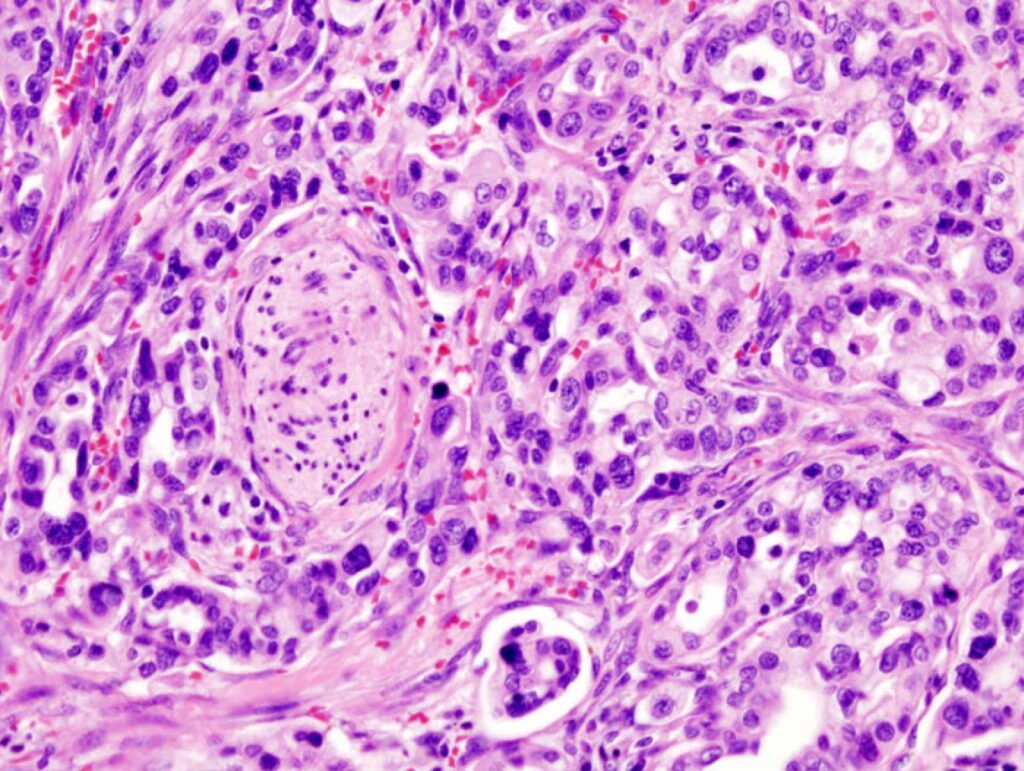

Uno studio su Nature indaga le primissime fasi dello sviluppo del tumore del pancreas, cercando d’identificare alterazioni molecolari precoci che indichino l’inizio della progressione tumorale. I risultati evidenziano mutazioni nel gene KRAS e che ogni precursore è un evento indipendente dagli altri: non sono futuri tumori, ma popolazioni che potrebbero in effetti darvi origine.

Crediti immagine: Wikimedia Commons. Licenza: CC attribution-sharealike 3.0 unported

Dei meccanismi mediante i quali una cellula normale cambia il suo status e prende la via della trasformazione tumorale sappiamo molto: mutazioni in geni coinvolti nel controllo del ciclo cellulare, della proliferazione, nella rimozione di basi danneggiate o inserite in modo scorretto dal DNA, mutazioni che rendono questi geni non funzionali o troppo funzionali. Sappiamo molto anche di tutti gli eventi che consentono a un tumore di crescere, invadere, infiltrare, collegarsi al circolo ematico, diventare resistente alle terapie, disperdere metastasi.

Uno studio su Nature indaga le primissime fasi dello sviluppo del tumore del pancreas, cercando d’identificare alterazioni molecolari precoci che indichino l’inizio della progressione tumorale. I risultati evidenziano mutazioni nel gene KRAS e che ogni precursore è un evento indipendente dagli altri: non sono futuri tumori, ma popolazioni che potrebbero in effetti darvi origine.

Crediti immagine: Wikimedia Commons. Licenza: CC attribution-sharealike 3.0 unported

Ricerca scientificaSaluteDei meccanismi mediante i quali una cellula normale cambia il suo status e prende la via della trasformazione tumorale sappiamo molto: mutazioni in geni coinvolti nel controllo del ciclo cellulare, della proliferazione, nella rimozione di basi danneggiate o inserite in modo scorretto dal DNA, mutazioni che rendono questi geni non funzionali o troppo funzionali. Sappiamo molto anche di tutti gli eventi che consentono a un tumore di crescere, invadere, infiltrare, collegarsi al circolo ematico, diventare resistente alle terapie, disperdere metastasi.”}]]